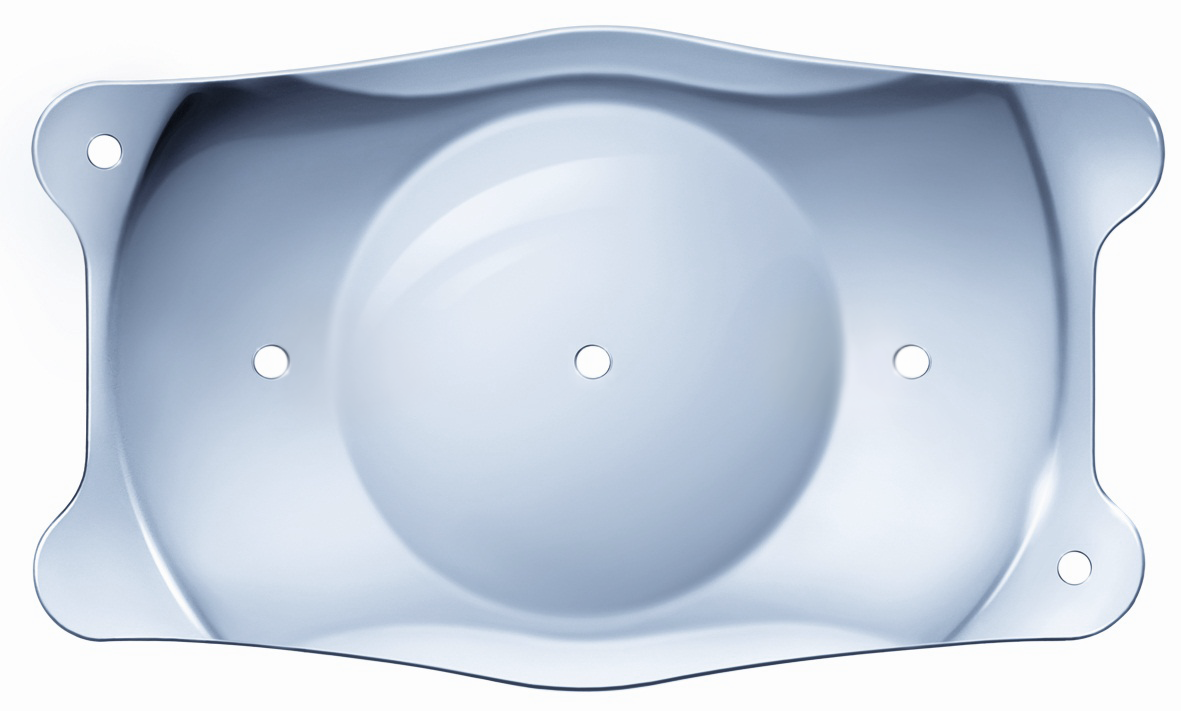

Product id: Lente intraocular on sale faquica

Lentes Intraoculares F quicas introducci n y complicaciones on sale, Iris Fixated Phakic Intraocular Lens Implantation on sale, Implantaci n de lentes intraoculares f quicos y f quicos t ricos on sale, Lentes intraoculares f quicas on sale, Lente intraocular f quico cirug a que permite dejar de usar on sale, Intraocular Lenses Incornea ENG on sale, Visian ICL lentes intraoculares f quicas on sale, Dr. Gonzalo Gallegos La implantaci n de lente intraocular on sale, Implantaci n de lentes intraoculares f quicos y f quicos t ricos on sale, Lentes F quicas oculares rea Oftalmol gica Avanzada on sale, Implante de Lentes Arbrayss L ser Oftalmolog a Pioneros en on sale, Lentes F quicas rea Oftalmol gica Avanzada Dr. Darchuk on sale, Lente Intraocular F quica ICL on sale, Precio Cirugia Intraocular Sale Online SAVE 51 factoria 4 7 on sale, Implante de lentes intraoculares todo lo que debes saber on sale, Correcci n de la alta miop a con implante de lente f quica ACR 128 on sale, Multimedia Dr. Luis Fernando Mej a Oftalm logo Medell n Colombia on sale, Lentes Intraoculares F quicas en Vista Mallorca Facorefractiva on sale, Lentes intraoculares f quicas ICL Cl nicas Tecnovision on sale, Lentes Intraoculares LIO T ricas Cl nica Oftalmol gica Santa on sale, Lente intraocular f quica de c mara anterior de fijaci n angular on sale, Miranza IOA LENTES F QUICAS ICL on sale, Qu son las Lentes F quicas rea Oftalmol gica Avanzada on sale, Lentes ICL o Lentes Intraoculares Ventajas e Indicaciones on sale, Lentes Intraoculares F quicas introducci n y complicaciones on sale, Las lentes intraoculares f quicas una soluci n en auge para on sale, Cirug a de Implante de Lente Intraocular F quico en Ibagu Tolima on sale, Implantaci n de lente intraocular de c mara anterior on sale, Multimedia Dr. Luis Fernando Mej a Oftalm logo Medell n Colombia on sale, Lente Intraocular F quico Curiel Visi n on sale, Lente F quica Dr. Fernando Mayorga on sale, Lente intraocular f quica fotograf as e im genes de alta on sale, Lentes intraoculares f quicas Wikipedia la enciclopedia libre on sale, Vista de Tecnolog as para la emetrop a Archivos Argentinos de on sale, Miop a hipermetrop a y astigmatismo Dr. Diego Croce on sale, Ceoval Centro Oftalmol gico de Valencia Sabes que la lente on sale, Cirug a de lente intraocular Dra. Elisa Nieto Torres on sale, Lentes intraoculares f quicas ICL IO ICO Barcelona on sale, Lente intraocular f quica fotograf as e im genes de alta on sale, Cirug a de catarata explante lente f quica PRL on sale, C mo se coloca el lente intraocular f quico Conoce todos los detalles on sale, Implante de Lente Intraocular Dr Gabriel Oliveros on sale, LENTE INTRAOCULAR Faquico Fijaci n En el Iris ppt descargar on sale, Lentes F quicas Cirurgia para miopia lentes intra oculares on sale, Cirug a de lente f quica Intraocular ICL Smart Laser Eye Center on sale, Dra. Paola Zurita Ferrel Cirujana Oftalm loga Qu son las on sale, Lentes F cicas Altas Ametropias on sale, Lente Faquico Torico en Paciente con Queratocono Operado de Anillos Intraestromales on sale, Cirug as de cambio de color de ojos e implantes de iris on sale, Lente intraocular f quica de c mara anterior de fijaci n angular on sale.

Lentes Intraoculares F quicas introducci n y complicaciones on sale, Iris Fixated Phakic Intraocular Lens Implantation on sale, Implantaci n de lentes intraoculares f quicos y f quicos t ricos on sale, Lentes intraoculares f quicas on sale, Lente intraocular f quico cirug a que permite dejar de usar on sale, Intraocular Lenses Incornea ENG on sale, Visian ICL lentes intraoculares f quicas on sale, Dr. Gonzalo Gallegos La implantaci n de lente intraocular on sale, Implantaci n de lentes intraoculares f quicos y f quicos t ricos on sale, Lentes F quicas oculares rea Oftalmol gica Avanzada on sale, Implante de Lentes Arbrayss L ser Oftalmolog a Pioneros en on sale, Lentes F quicas rea Oftalmol gica Avanzada Dr. Darchuk on sale, Lente Intraocular F quica ICL on sale, Precio Cirugia Intraocular Sale Online SAVE 51 factoria 4 7 on sale, Implante de lentes intraoculares todo lo que debes saber on sale, Correcci n de la alta miop a con implante de lente f quica ACR 128 on sale, Multimedia Dr. Luis Fernando Mej a Oftalm logo Medell n Colombia on sale, Lentes Intraoculares F quicas en Vista Mallorca Facorefractiva on sale, Lentes intraoculares f quicas ICL Cl nicas Tecnovision on sale, Lentes Intraoculares LIO T ricas Cl nica Oftalmol gica Santa on sale, Lente intraocular f quica de c mara anterior de fijaci n angular on sale, Miranza IOA LENTES F QUICAS ICL on sale, Qu son las Lentes F quicas rea Oftalmol gica Avanzada on sale, Lentes ICL o Lentes Intraoculares Ventajas e Indicaciones on sale, Lentes Intraoculares F quicas introducci n y complicaciones on sale, Las lentes intraoculares f quicas una soluci n en auge para on sale, Cirug a de Implante de Lente Intraocular F quico en Ibagu Tolima on sale, Implantaci n de lente intraocular de c mara anterior on sale, Multimedia Dr. Luis Fernando Mej a Oftalm logo Medell n Colombia on sale, Lente Intraocular F quico Curiel Visi n on sale, Lente F quica Dr. Fernando Mayorga on sale, Lente intraocular f quica fotograf as e im genes de alta on sale, Lentes intraoculares f quicas Wikipedia la enciclopedia libre on sale, Vista de Tecnolog as para la emetrop a Archivos Argentinos de on sale, Miop a hipermetrop a y astigmatismo Dr. Diego Croce on sale, Ceoval Centro Oftalmol gico de Valencia Sabes que la lente on sale, Cirug a de lente intraocular Dra. Elisa Nieto Torres on sale, Lentes intraoculares f quicas ICL IO ICO Barcelona on sale, Lente intraocular f quica fotograf as e im genes de alta on sale, Cirug a de catarata explante lente f quica PRL on sale, C mo se coloca el lente intraocular f quico Conoce todos los detalles on sale, Implante de Lente Intraocular Dr Gabriel Oliveros on sale, LENTE INTRAOCULAR Faquico Fijaci n En el Iris ppt descargar on sale, Lentes F quicas Cirurgia para miopia lentes intra oculares on sale, Cirug a de lente f quica Intraocular ICL Smart Laser Eye Center on sale, Dra. Paola Zurita Ferrel Cirujana Oftalm loga Qu son las on sale, Lentes F cicas Altas Ametropias on sale, Lente Faquico Torico en Paciente con Queratocono Operado de Anillos Intraestromales on sale, Cirug as de cambio de color de ojos e implantes de iris on sale, Lente intraocular f quica de c mara anterior de fijaci n angular on sale.